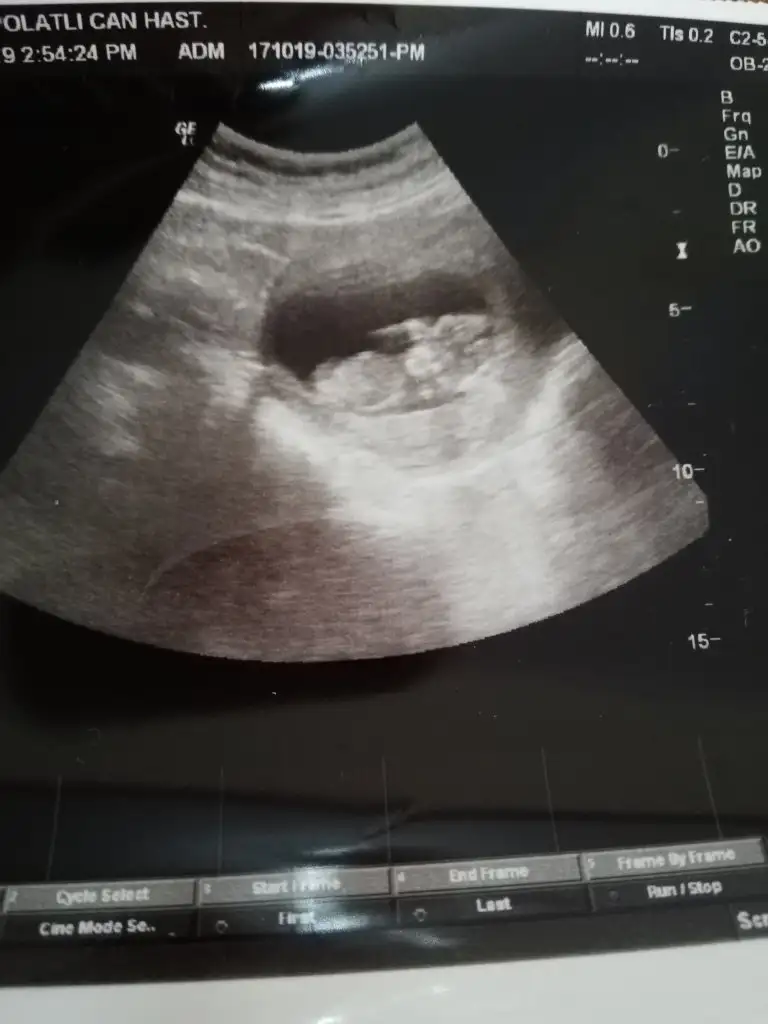

Simdiki ekledigim 9 haftalik

Merhaba riskli bir gebelik yaşıyorum. Öncelikle dualarınıza ihtiyacım var. Cinsiyet tahminizi alabilir miyim ?